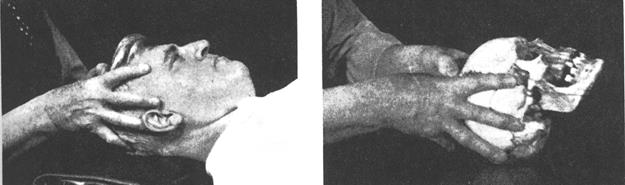

Рис.11.3. Подход со стороны свода к сфенобазилярному симфизу.

Рис.11.4 Лобнозатылочный подход к сфенобазилярному симфизу.

б) Лобнозатылочный подход

Кисть одной руки чашеобразно расположена под затылочной чешуей медиальнее латеральных углов. I и II пальцы другой руки на больших крыльях основной кости, ладонь - на чешуе лобной кости. Ни в коем случае не сдавливайте медиально крылья основной кости кончиками пальцев!

Флексия возникает при приведении лобной области в вентрокаудальное положение и затылочной кости в вентрокраниальное положение посредством вращения основной и затылочной костей вокруг их фронтальных осей. Вращение затылочной кости не является обязательным. Бывает достаточно лишь одного движения основной кости.

а) Подход со стороны свода.

1-е пальцы соединены над черепом, но не касаются его,что даёт возможность правильного использования силы мышц длинных сгибателей больших пальцев и глубоких сгибателей пальцев. Остальные пальцы располагаются следующим образом: II - на латеральных поверхностях больших крыльев. III - непосредственно перед ушными раковинами. IV- позади ушных раковин. V - на затылочной чешуе. При помощи подушечек проксимальных фаланг (но не верхушками пальцев) приведите краниосакральный механизм во флексию, мысленно представляя себе фронтальные оси основной изатылочной костей, вокруг которых осуществляетсяих вращение (для основной кости - через центр тела и середины скуловых отростков, для затылочной - над яремным отростком на уровне симфиза и через середину линии, соединяющей asterion и верхушку сосцевидного отростка).

Флексия вызывается приведением сосцевидного и основного углов теменных костей в вентролатеральном направлении (в наружную ротацию). Одновременно II -е пальцы могут привести латеральные углы лобных костей в вентролатеральное положение, что обязательно приведёт в движение основную и затылочную кости.